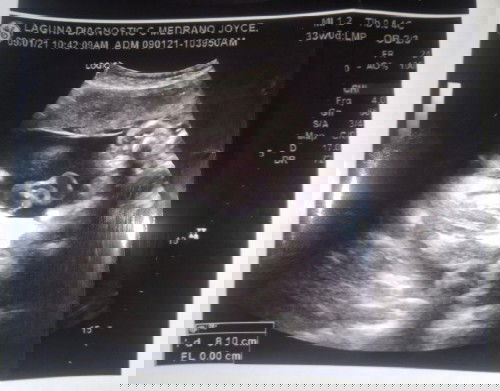

Baby girl😊

Tanong lang Po paano Po Malaman Kung talagang baby girl Po Yung baby ko?